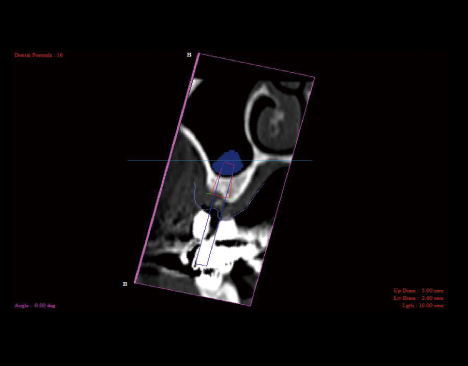

インプラント

歯科インプラントとは、失った歯の部分にチタン製の人工歯根(インプラント)を埋め入れて、歯本来の機能や見た目を取り戻す治療方法のことをいいます。 失った歯の部分を治療しますので、周囲の歯に負担をかけることがありません。 また、これまでにあった歯と同じような役割を果たしますので、噛む力を分散させ、残っている自分の歯を守ることにもなります。